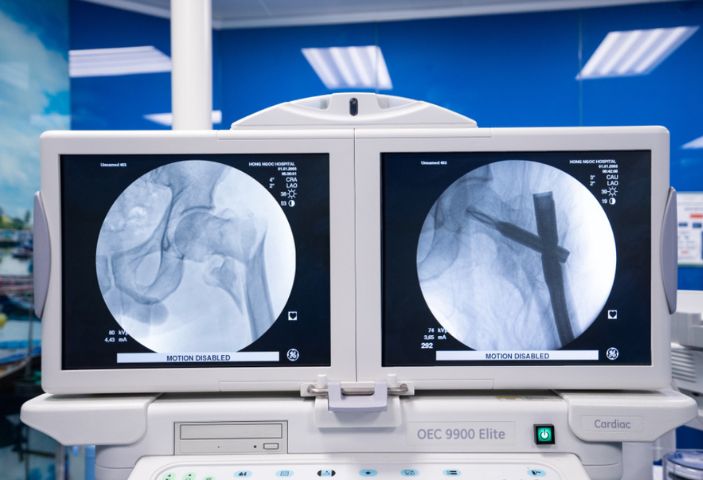

- Cố định trong hay Kết hợp xương sinh học

Phẫu thuật để sắp xếp lại xương từ bên trong và sau đó cố định bằng ốc vít hoặc mảnh kim loại. Phù hợp cho trường hợp gãy xương phức tạp, đảm bảo ổn định và tái tạo xương chính xác.

+ Đường mổ nhỏ chỉ từ 0.5 – 3cm cho sẹo nhỏ thẩm mỹ, ít xâm lấn mô mềm, ít gây mất máu, bảo tồn được các mạch máu nuôi ổ gãy, hạn chế tối đa nhiễm trùng.

+ Sử dụng đinh, nẹp vít chất liệu an toàn, tương thích với cơ thể, cung cấp độ vững khi vận động, kích thích hình thành tế bào xương và tế bào sụn cùng các sợi collagen, giúp xương liền tự nhiên, hồi phục vận động sau 1 ngày phẫu thuật.

+ Kết hợp thiết bị y tế hiện đại: bàn mổ chỉnh hình, máy C-arm,… xác định chính xác vị trí gãy, nắn xương về đúng vị trí, tránh biến chứng sau phẫu thuật.